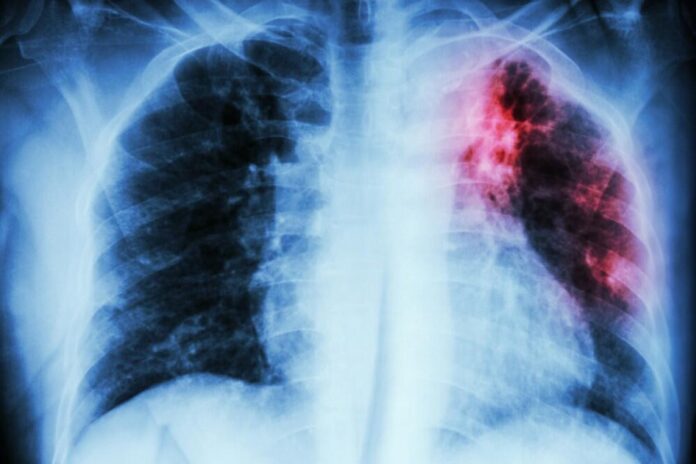

Azərbaycanda vərəmlə xəstələnmə dinamikası (100.000 əhaliyə): 2015 ildə bu göstərici 41.1 olan halda, 2025 ildə – 21,5 qeyd olunub.

Azərbaycanda ilkin ağciyər vərəmli xəstələr arasında TDM-nin (Turşuya Davamlı Mikobakteriya – Vərəm Mikobakteriyası) aşkar olunması dinamikası 2015 ildə 53% olduğu halda, 2025 ildə bu göstərici 86% çatıb.